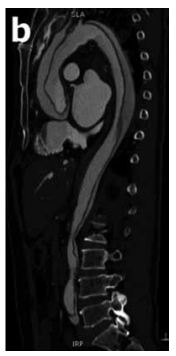

Homem, 58 anos, com antecende de hipertensão de longa data, procura atendimento médico com queixa de dor torácica, súbita, em facada, que iniciou há duas horas. Dá entrada no hospital com pressão arterial de 200 X 120 mmHg e frequência cardíaca de 100 bpm. O eletrocardiograma não apresenta alterações isquêmicas agudas. Opta-se pela realização de angiotomografia de tórax, ilustrada a seguir.

Assinale a alternativa que apresenta a classificação e conduta corretas, respectivamente